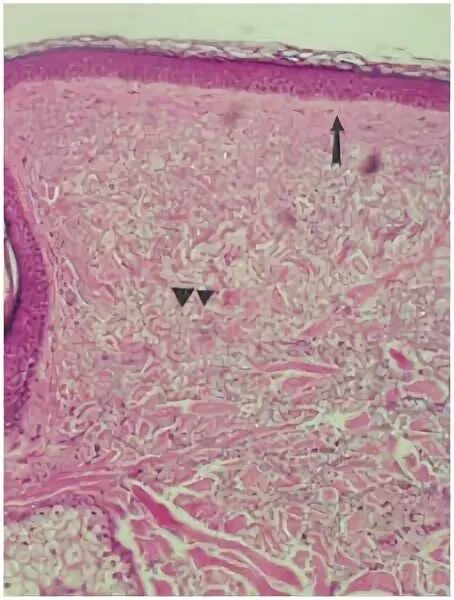

Солнечный эластоз